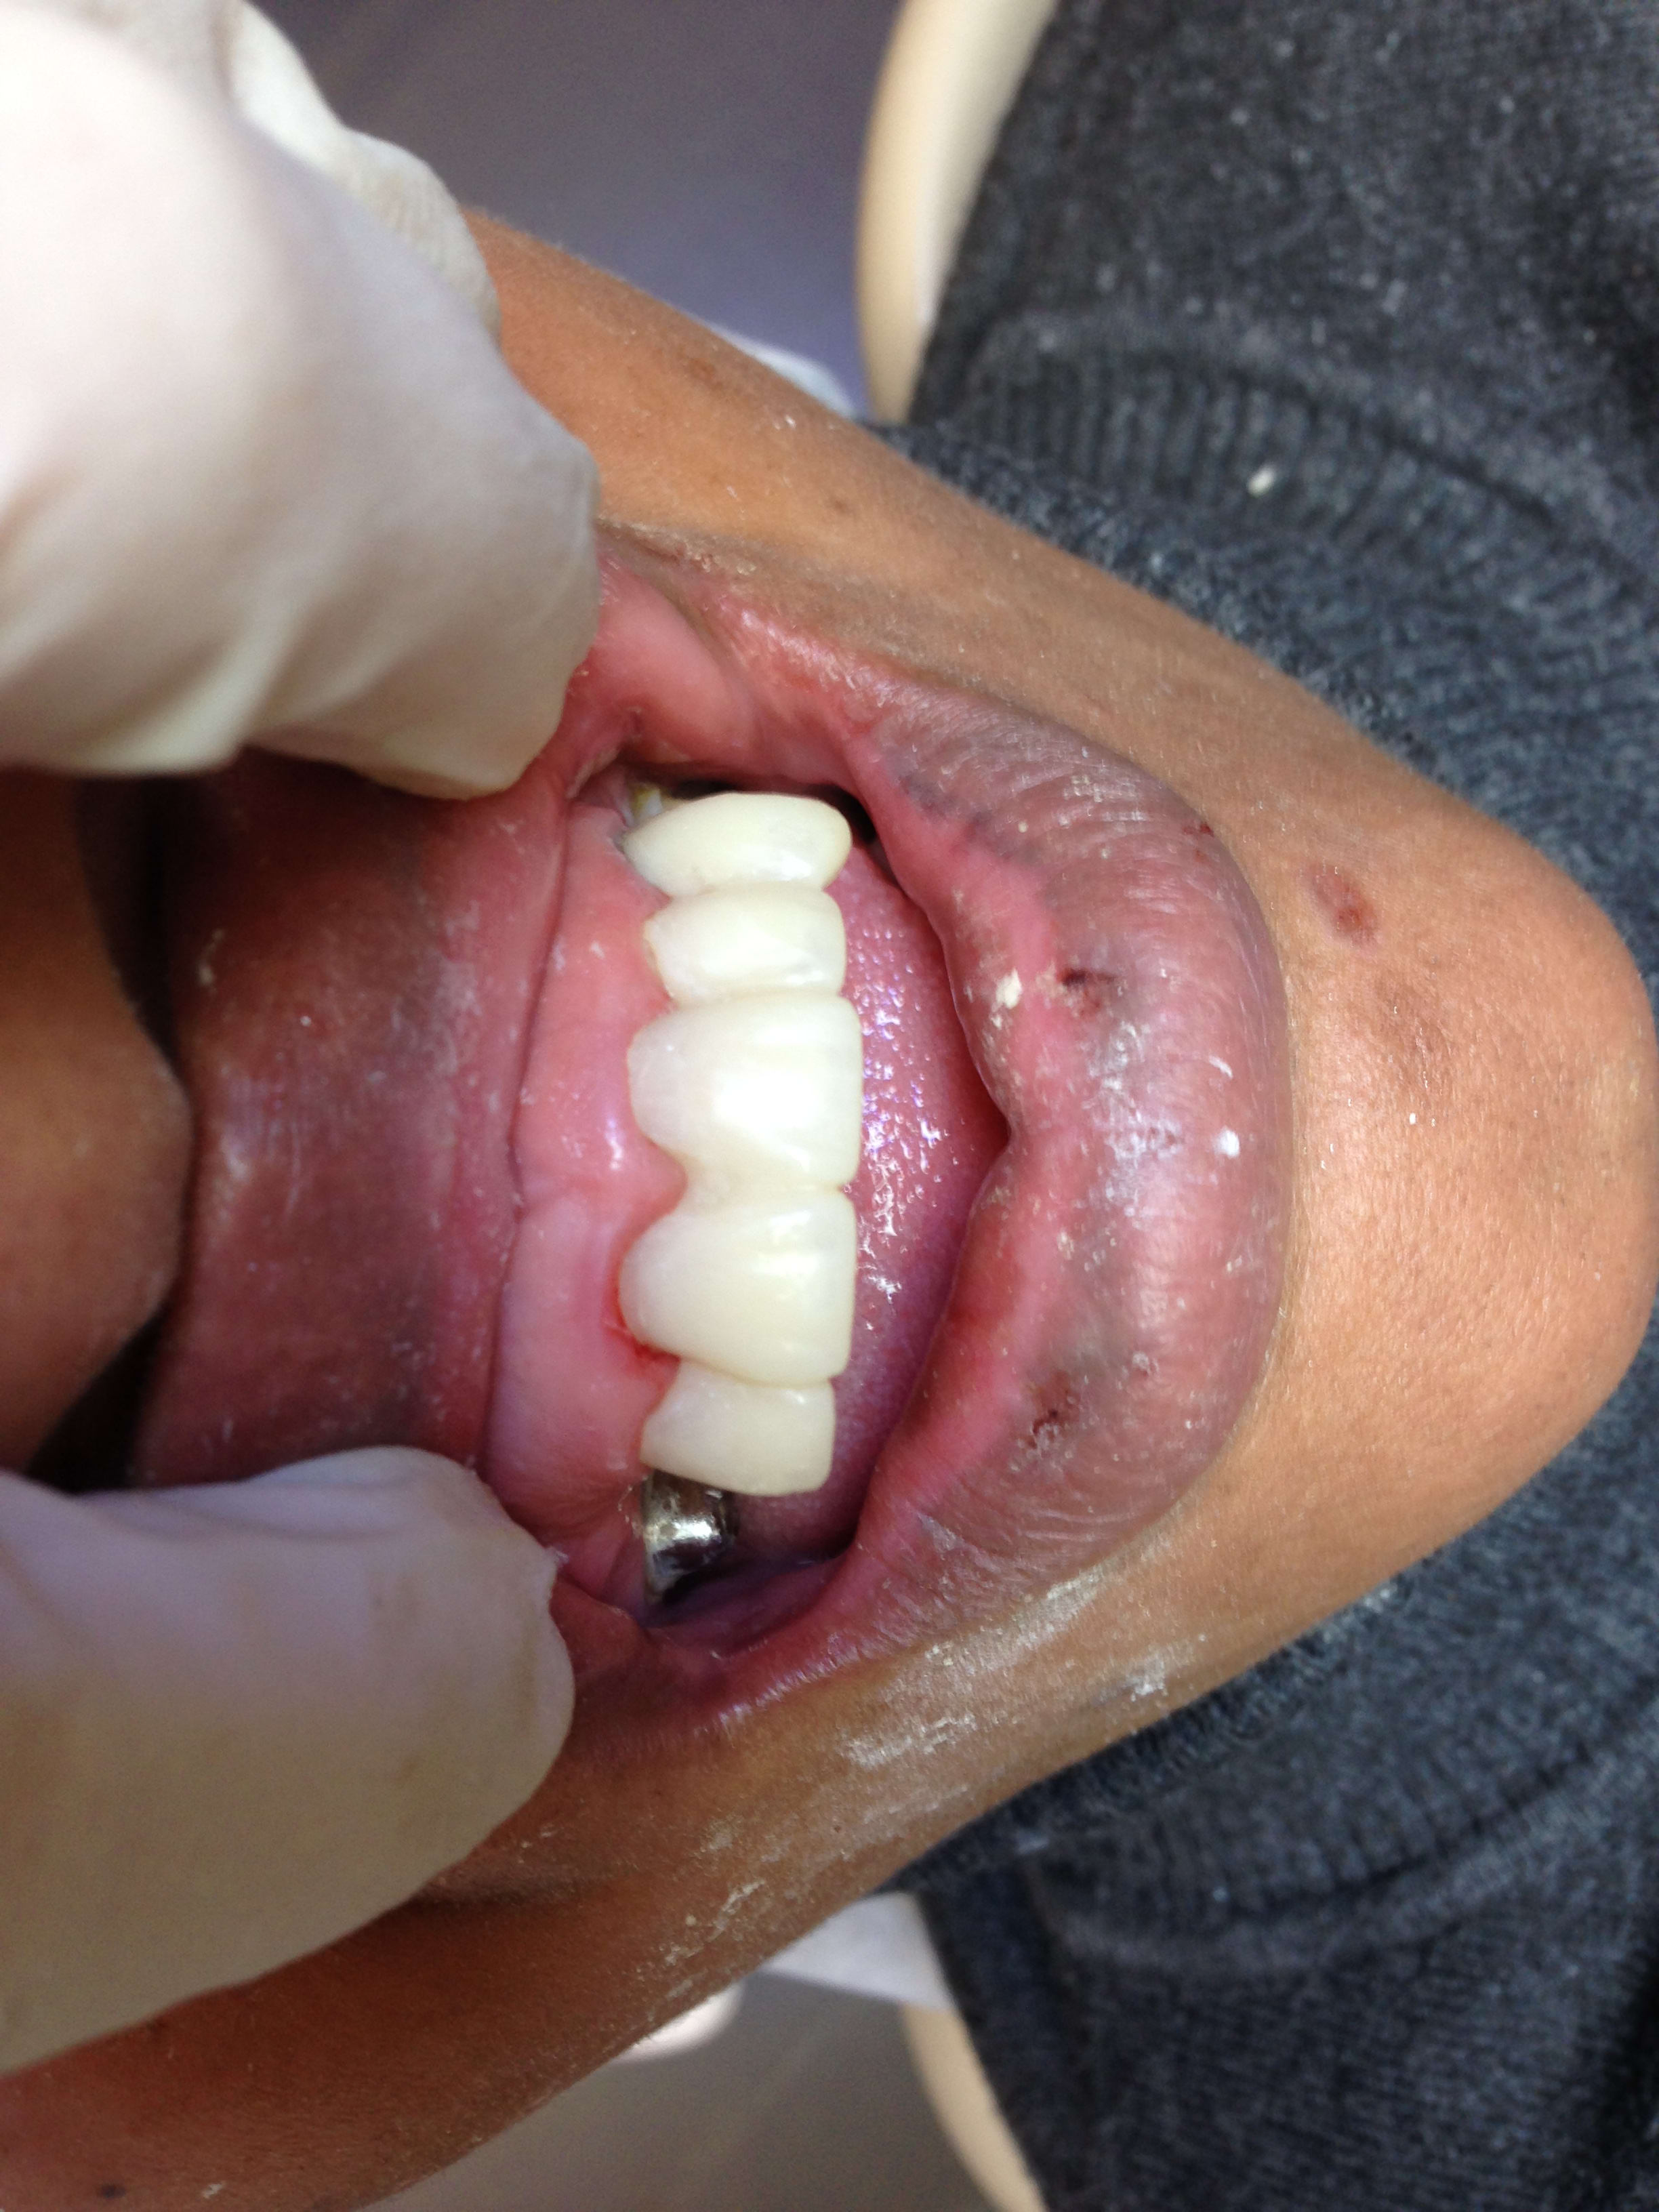

Pour mettre un peu d'eau dans le moulin à Junior... : patient vu ce matin en urgence, avec une belle nécrose sous un joli onlay céramique très esthétique, posé en 2014.

Screenshot331 ufufx5 - Eugenol

Screenshot332 h9zbed - Eugenol